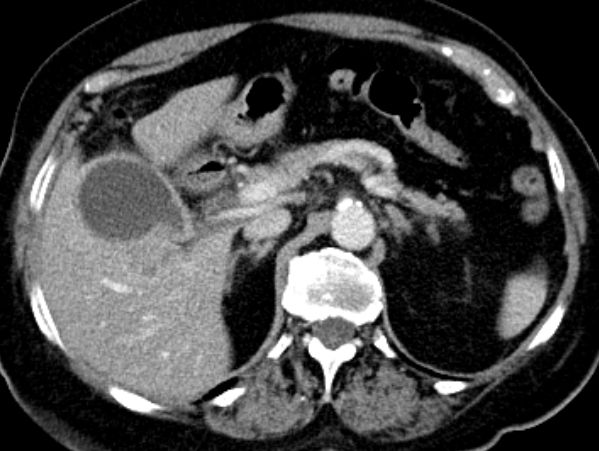

| CT | 81-jähriger Mann mit schmerzlosem Ikterus. Tumor in der Hepatikusgabel. CT nach Stent, portalvenöse Phase: Erweiterte Gallengänge des rechten Lebenlappens, RF im Leberhilus.![]() | |||